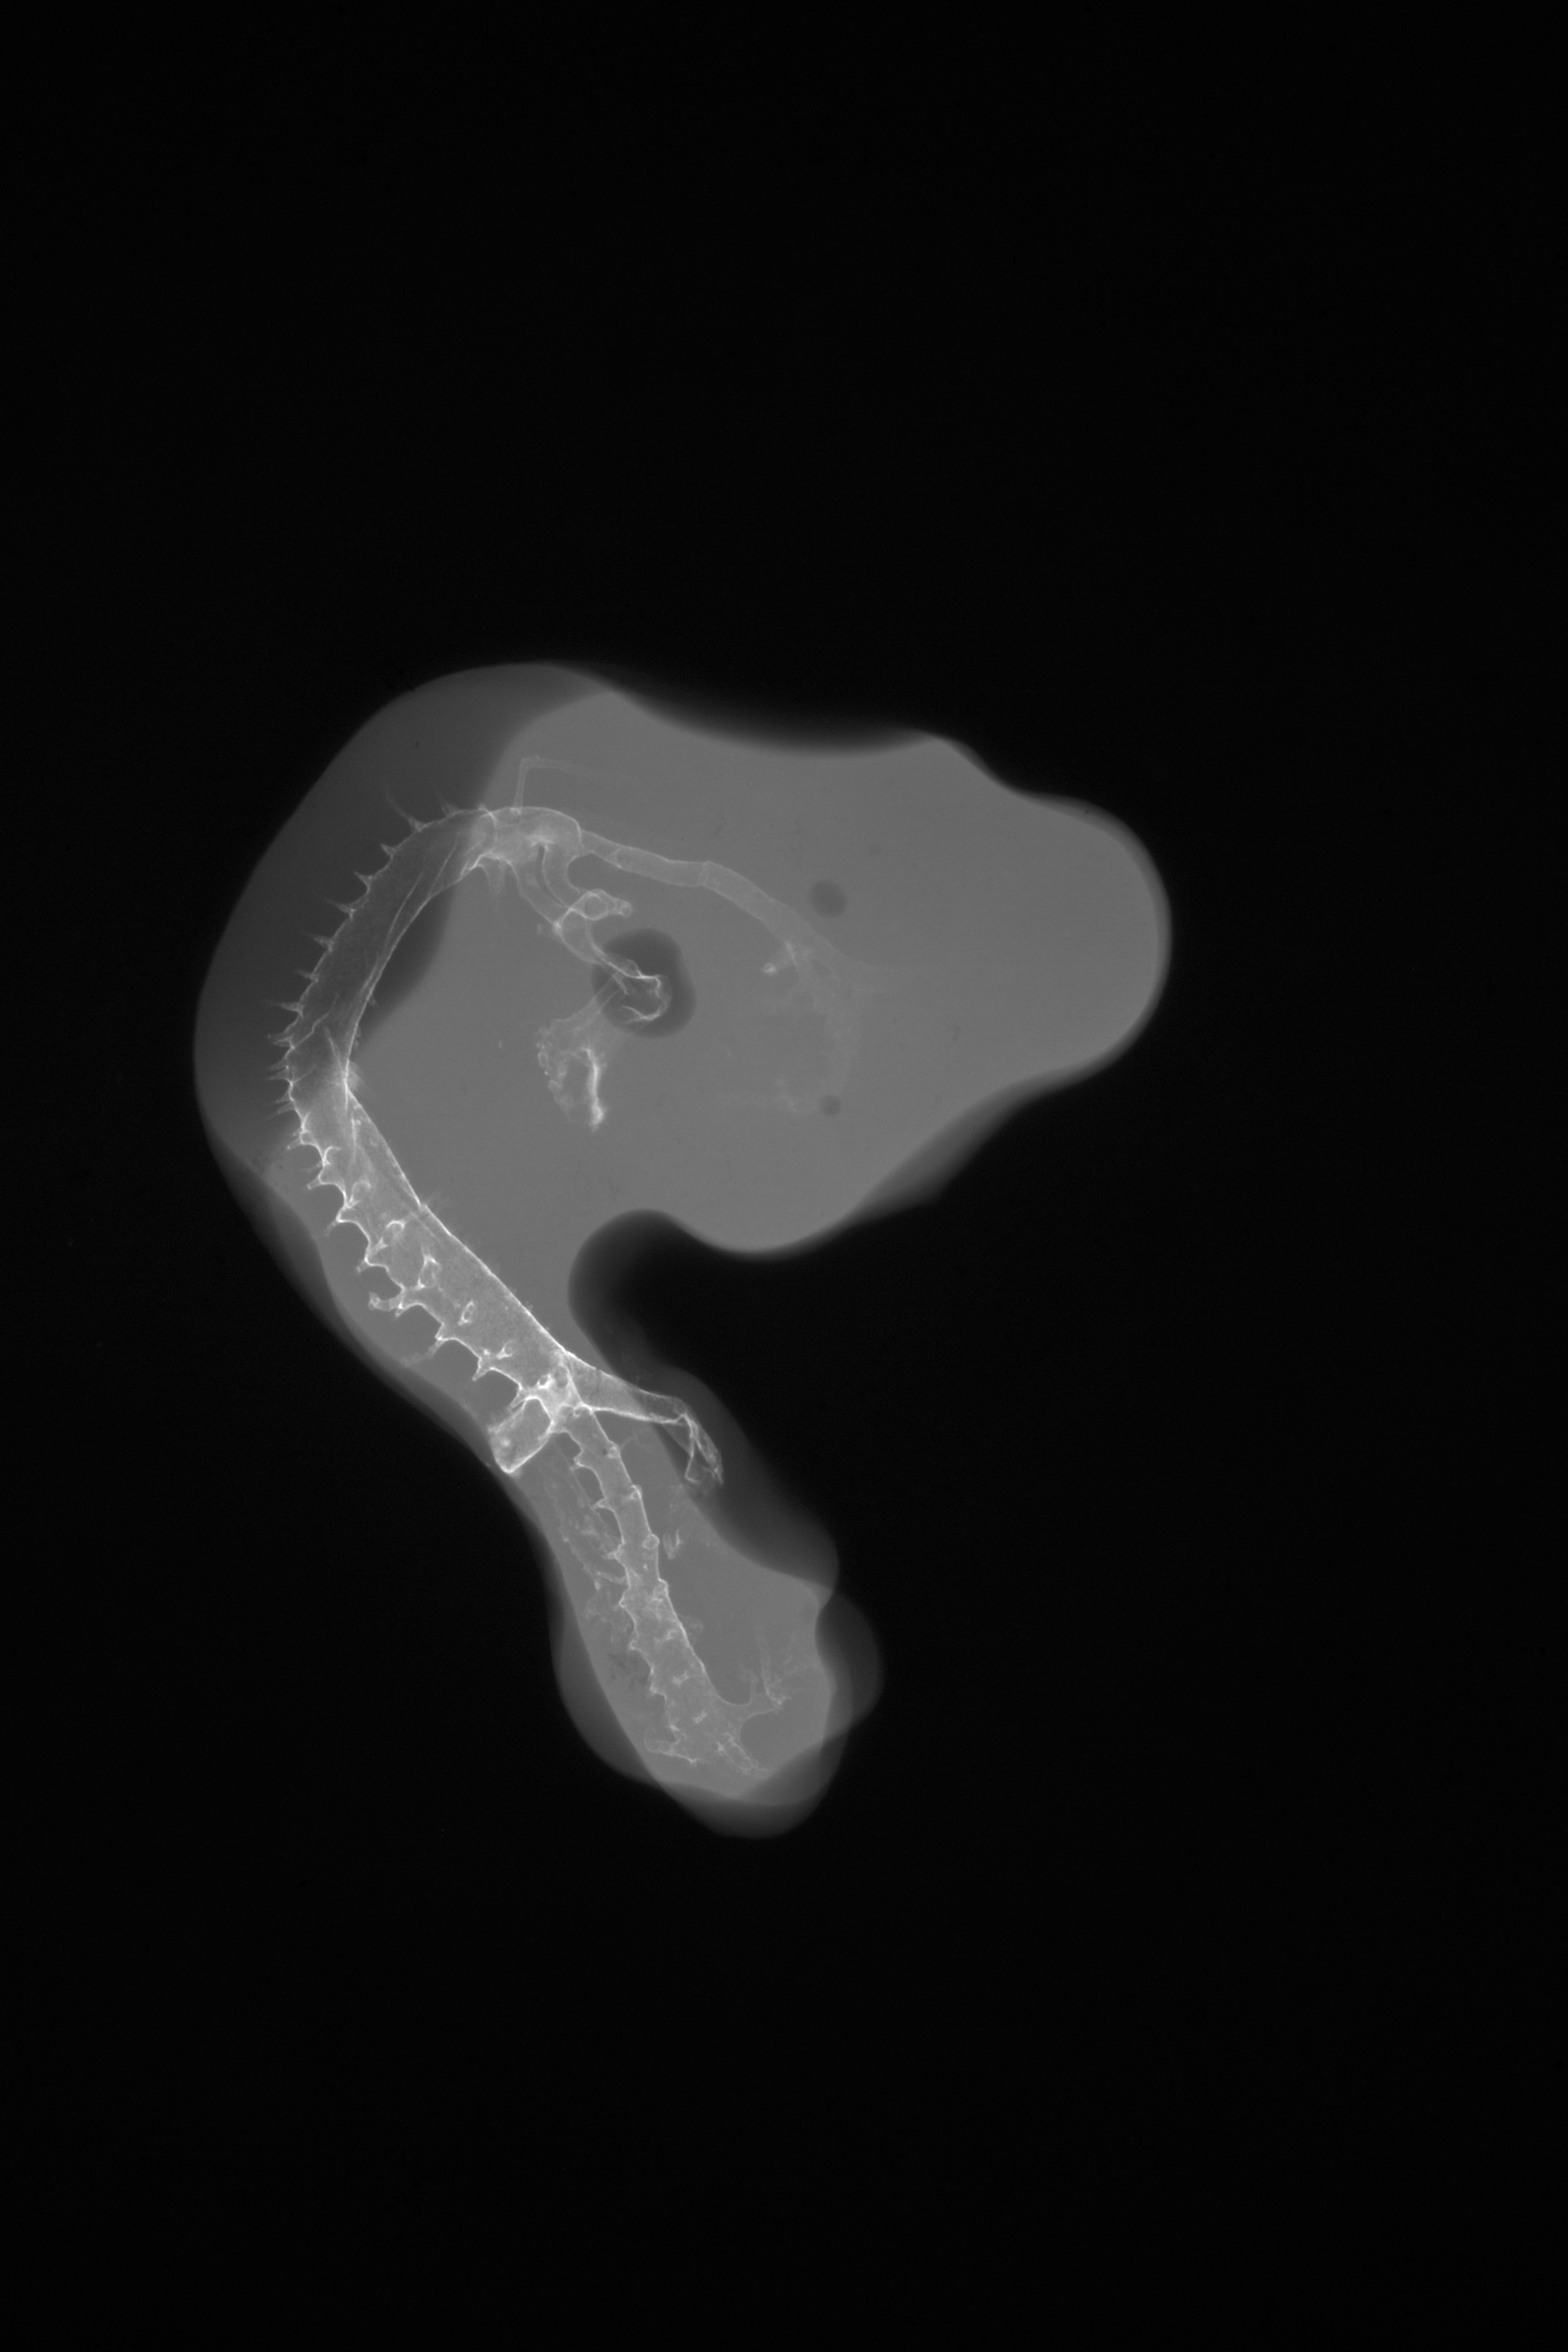

X-Ray Micrographs